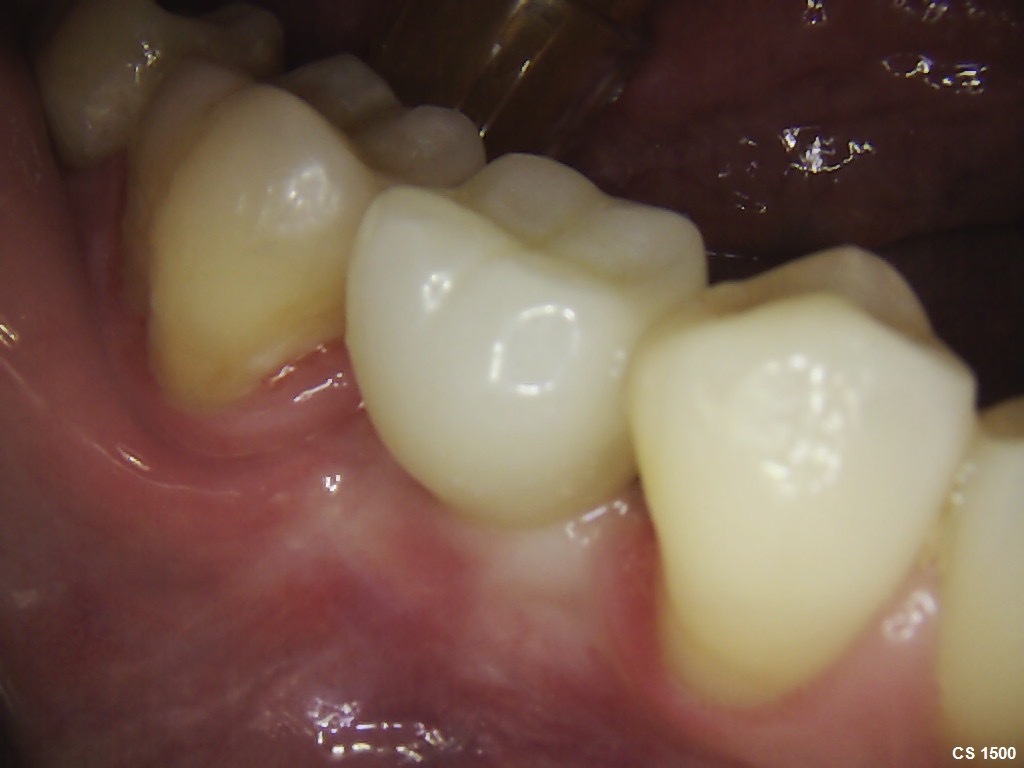

After 6 months of successful

orthodontic treatment, we were finally able to place the implant and the

provisional crown. After 4 months of ingrowth, aligners were removed and a full

ceramic crown was placed. The treatment was successfully completed!✋🏽😉